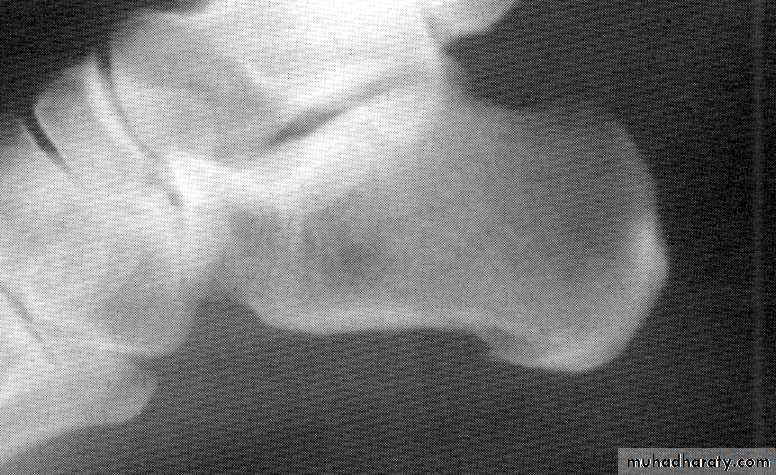

The pathology of the disease process often lead to destruction of articular cartilage& ankylosis(fusion) of the joints .

The inflammation and thickening of the synovial membranes cause irreversible damage to the joint capsule and articular cartilage as these structures replaced by scar like tissue called Pannus.